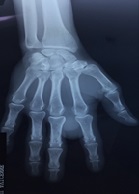

Juxta Articular Myxoma of the Hand: A Case Report and Review of the Literature

Mohammed Reda Fekhaoui1*, Ismail Kabbaj1, Laila El’otmani1, Reda-Allah Bassir2, Moncef Boufettal2, Mustapha Mahfoud1, Mohammed Saleh Berrada1